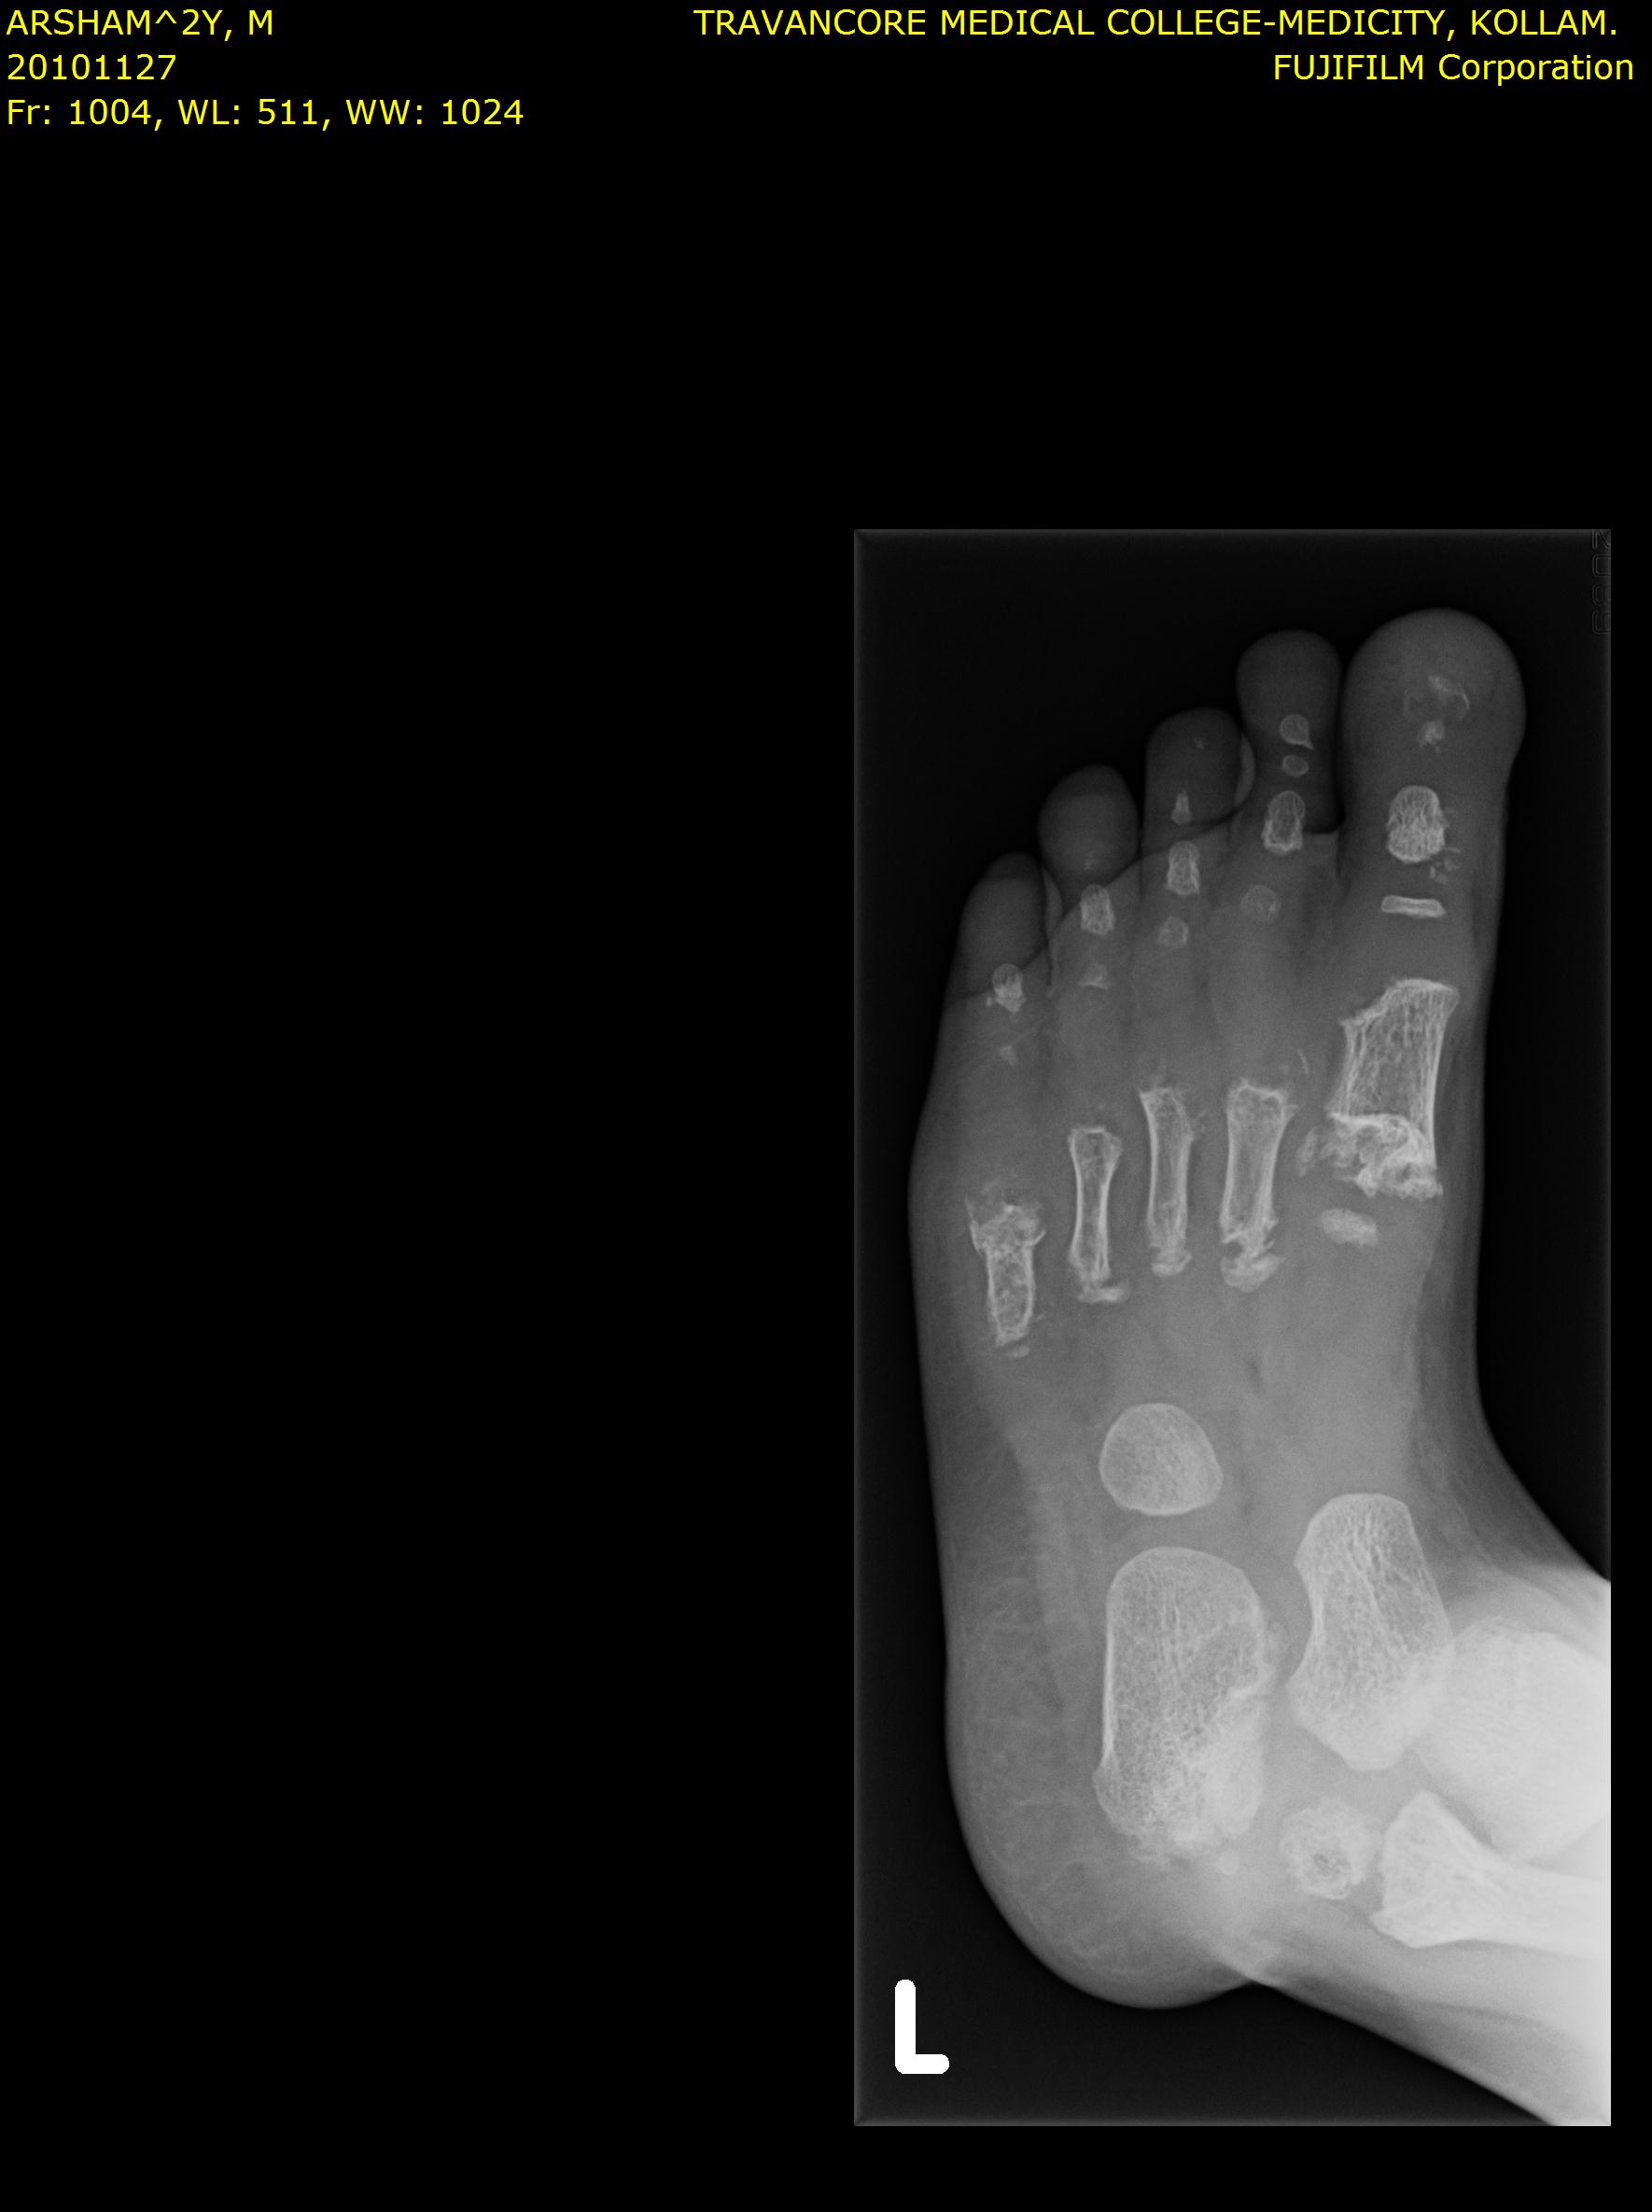

Here we share radiographic images to help with diagnosis of Jansen's disease:

Jansen's patients show extreme disorganization of the metaphyses of the long bones and of the metacarpal and metatarsal bones in sharp contrast to the almost normal appearance of the epiphyseal centers, which on x-ray appear widely separated from the long bones. The chin is receding. The fingers, especially the distal phalanges, are very short. The spine, pelvis, and lower legs are distorted.